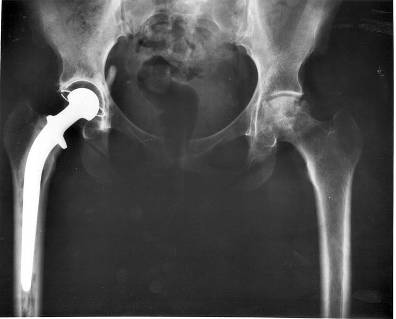

Эндопротезирование суставов

Это замена компонентов сустава эндопротезами, повторяющими форму нормального сустава и воспроизводящими функцию сустава. Часто эндопротезирование является единственным методом, способным восстановить утраченную подвижность сустава и ликвидировать боль в суставе. Уже через один-два месяца после протезирования сустава пациент может вернуться к активной жизни. Установленные внутри тела человека они способны служить 15-20 и даже 30 лет, а при износе сустава, его можно снова заменить. В мире каждый год производится имплантация около одного миллиона тазобедренных и более чем полмиллиона коленных эндопротезов.

В настоящее время существуют протезы для тазобедренных, коленных, плечевых, локтевых суставов и даже для суставов пальцев рук. Они производятся из металла, керамики, особо прочной пластмассы.